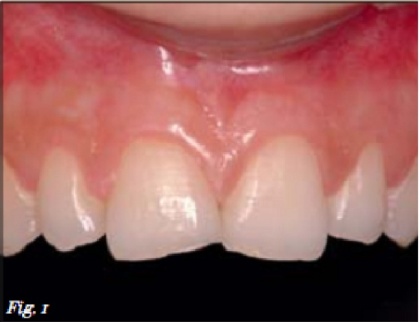

Bệnh nhân nữ 27 tuổi đến phòng khám với tình trạng bị mòn nặng các răng cửa trên (Hình 1). Cô ấy nói rằng, hai năm nay, những răng cửa giữa của cô ấy ngày càng nhỏ đi và hình dạng của nó dần thay đổi. Nha sĩ phát hiện ra rằng cô bị mòn răng là do tật nghiến răng vào ban đêm.

Bệnh nhân yêu cầu điều trị tật nghiến răng và khôi phục lại hình dạng răng như ban đầu. Lúc đầu, bệnh nhân được khám lâm sàng và chụp XQ; Tình trạng ban đầu đã được ghi lại bằng hình ảnh. Sau đó, lấy mẫu nghiên cứu. Phương án được chọn là trám tái tạo để giữ tối đa mô răng (điều trị xâm lấn tối thiểu).